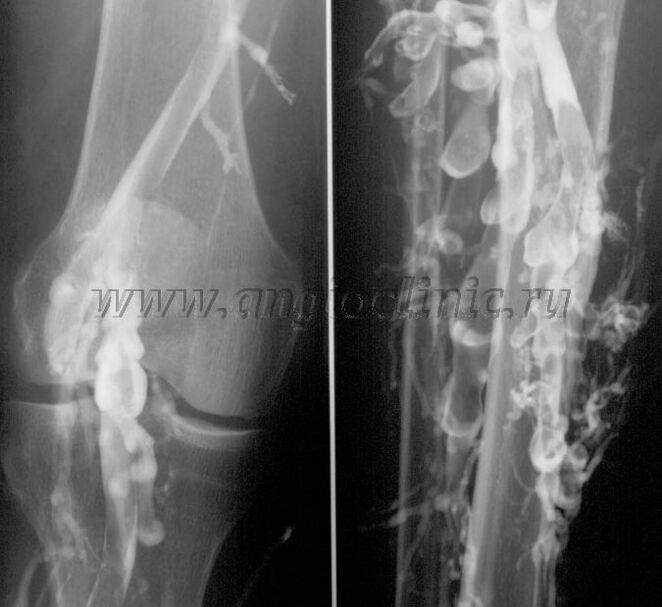

Velografia a contrasto

Solitamente per una diagnosi completa della patologia venosa è sufficiente un esame ecografico. Tuttavia, in alcuni casi è necessario studiare la connessione tra la condizione del sistema venoso profondo e quello superficiale, soprattutto nei casi di recidiva di vene varicose e vene varicose secondarie.

Per risolvere questi problemi viene utilizzato un esame radiografico con contrasto. Vengono perforate le vene safene e viene somministrato il mezzo di contrasto. Sul monitor della macchina a raggi X si osserva il movimento del mezzo di contrasto e si effettuano tutti i test e le proiezioni necessarie. Attualmente la venografia viene utilizzata solo molto raramente per le vene varicose.